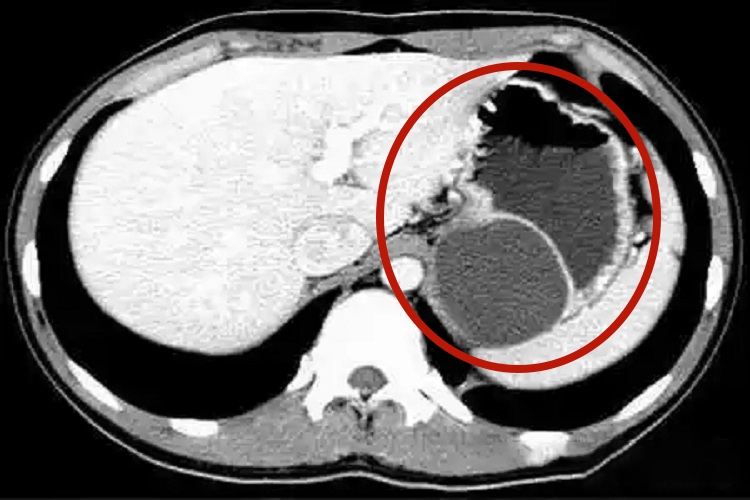

胃囊肿患者可无明显症状,也可出现上腹不适或疼痛。对于发生在贲门部较大的囊肿可引起吞咽困难,发生在幽门处可引起梗阻。胃囊肿患者进行内镜检查可见圆形或柱状隆起肿物,大小不定,表面光滑。